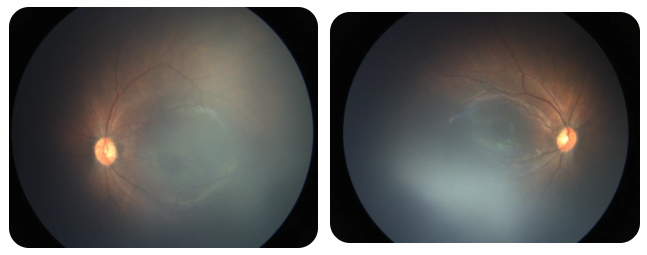

廈門眼科中心黎曉新名醫(yī)工作室曾接診一名31周出生的早產(chǎn)兒,出生體重僅1300克。由于家長缺乏篩查意識,直到孩子5個(gè)月大時(shí)眼睛仍不會追光,才前來就診。檢查發(fā)現(xiàn),患兒ROP已進(jìn)展至4B期,因纖維血管增殖牽拉導(dǎo)致視網(wǎng)膜脫離,錯(cuò)過了最佳治療窗口。盡管黎曉新教授團(tuán)隊(duì)成功實(shí)施了玻璃體切割手術(shù),孩子的視力仍存在不可逆損傷。此后,孩子開啟了長期隨診復(fù)查、治療的“護(hù)眼征程”,目前其右眼矯正視力為0.6,左眼為0.8。

近期術(shù)前檢查:

早產(chǎn)兒視網(wǎng)膜病變

術(shù)后復(fù)查:

相比之下,另一位早產(chǎn)寶寶在出生5周后,生命體征穩(wěn)定之時(shí),便在產(chǎn)科醫(yī)生的建議下轉(zhuǎn)診至廈門眼科中心。經(jīng)篩查確診為Ⅲ期ROP,黎曉新教授團(tuán)隊(duì)及時(shí)為其進(jìn)行了激光治療。半年后復(fù)查顯示,寶寶的視網(wǎng)膜血管發(fā)育正常,視力發(fā)育與足月兒童無異。